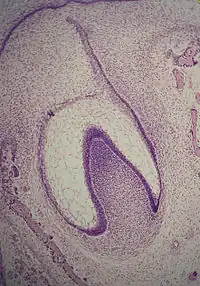

A: enamel organ

B: dental papilla

C: dental follicle

The tooth germ is an aggregation of cells that eventually forms a tooth.[2] These cells are derived from the ectoderm of the first pharyngeal arch and the ectomesenchyme of the neural crest.[1][3][4] The tooth germ is organized into three parts: the enamel organ, the dental papilla and the dental sac or follicle.